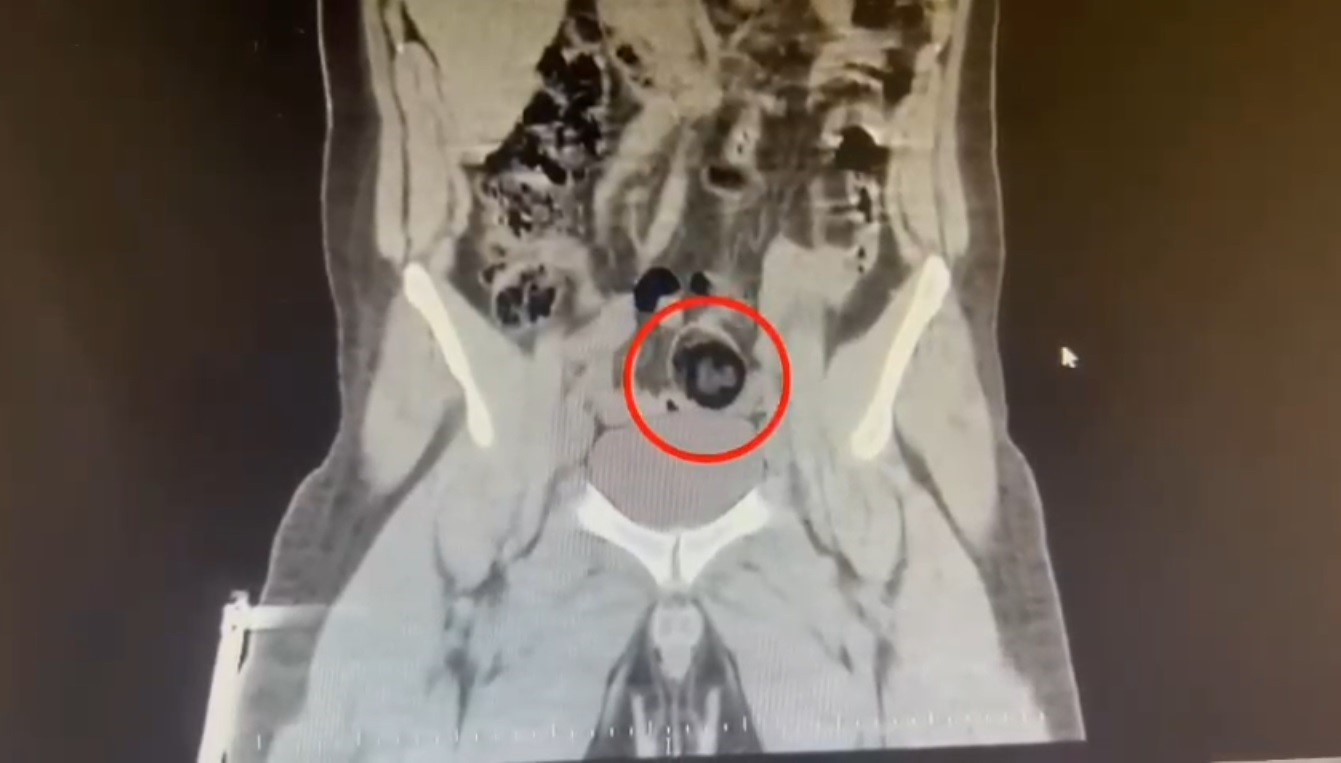

Kars Emniyet Müdürlüğü Narkotik Suçlarla Mücadele Şube Müdürlüğünce, savcılık koordinesinde kent merkezinde uluslararası uyuşturucu madde ticareti yapan kurye şahıslara yönelik operasyon düzenlendi. Bu kapsamda narkotik ekiplerince durdurulan yolcu otobüsünde İranlı kurye yakalanarak gözaltına alındı. Şüpheli hareketler sergilen kurye götürüldüğü hastanede yapılan iç beden muayenesinde makatında cisim olduğu anlaşıldı. Kuryenin makatındaki 105,98 gram metamfetamin gerçekleştirilen cerrahi müdahaleyle çıkarıldı. Gözaltına alınarak emniyete getirilen kurye, çıkarıldığı mahkemece "TCK-188 uyuşturucu veya uyarıcı madde imal ve ticareti yapmak" suçundan tutuklanarak cezaevine gönderildi.